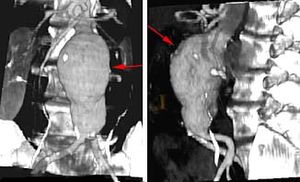

تمدد الأوعية الدموية يمكن أَنْ يكتشف بالفحص، بإستخدام صور الأشعة السينية للصدر أو للمعدة ، أَو بإستعمال التصوير بإستخدام النظائر المشعة أو الموجات فوق السمعية. يمكن أيضا أستعمال تصوير الرنين المغناطيسي، أو سي تي سكان tomographycomputed tomography (CT) scanning.

- في أجزاء الشريان الأبهر. الشريان الأبهر يحمل الدم من القلب إلى أجزاء أخرى من الجسم. تمدد الأوعية الدموية الأبهري يمكن أنْ يحدث في المنطقة أسفل المعدة (تمدد أوعية دموية بطني) أو في الصدر (تمدد أوعية دموية صدري). تمدد الأوعية الدموية البطني الأبهري يقع عادة تحت الكلى.